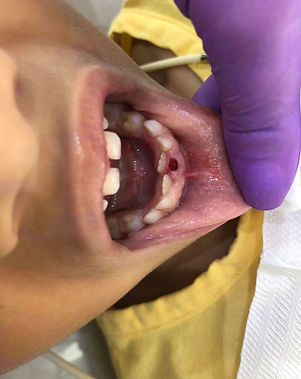

1) Ulectomia é um procedimento cirúrgico simples, realizado na gengiva, onde se remove os tecidos que estão revestindo a porção oclusal/incisal (parte de cima) de um dente, estruturas essas que estão impedindo o mesmo de nascer. A técnica abre um caminho para o dente romper na boca e assim se posicionar no local correto.